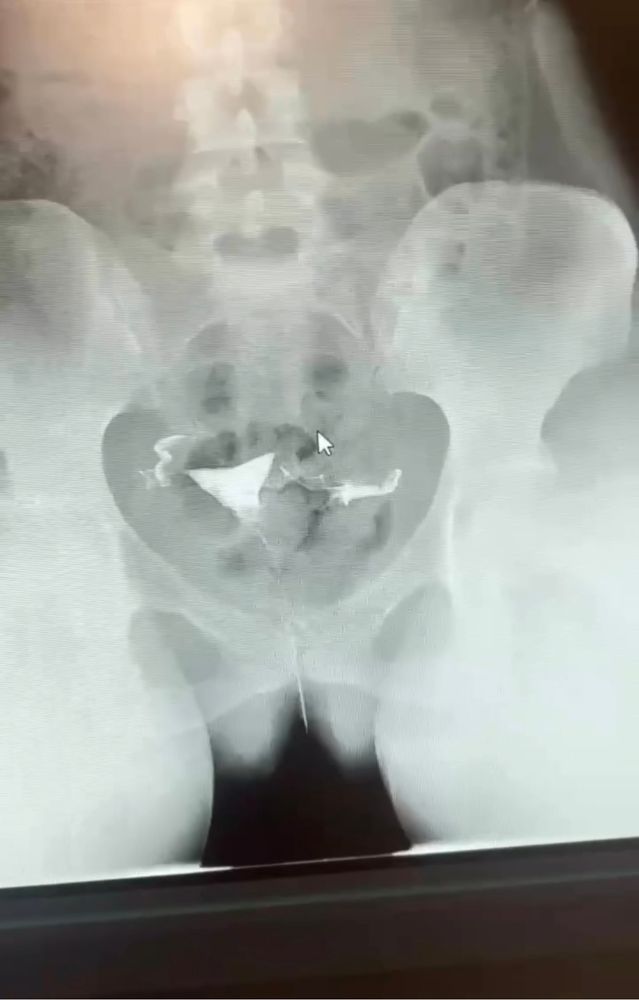

Гсг, что можете сказать по фото

ГСГ, ЭХО, МСГ, Фертилоскопия

Делала гсг, заключение еще не получила. Кто нибудь разбирается?